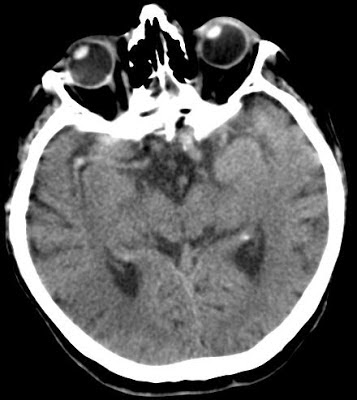

Acute ischemic stroke Szerző: admin | dec 27, 2012 | Brain, Ischemic stroke | Nincsenek hozzászólások hyperdens media sign (D0) ischemic infarction – right MCA territory (D5) 6911612012.12.13.